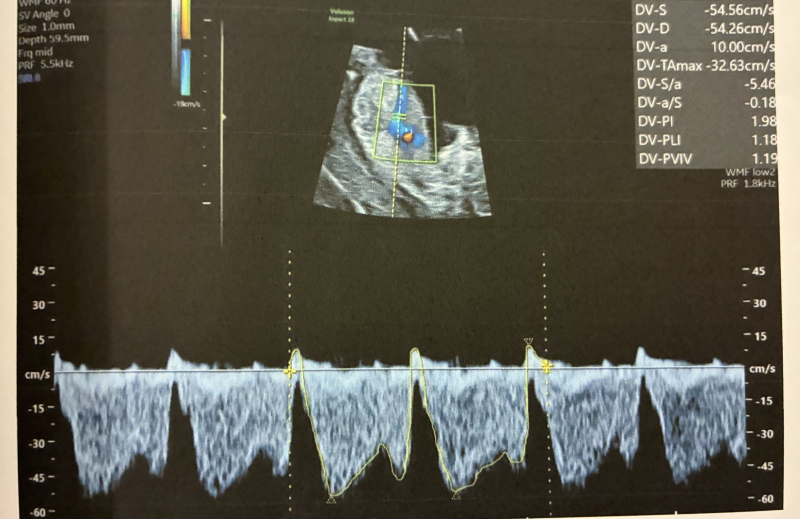

•静脈管(DV)でA波逆転が疑われる(Pl 1.980)